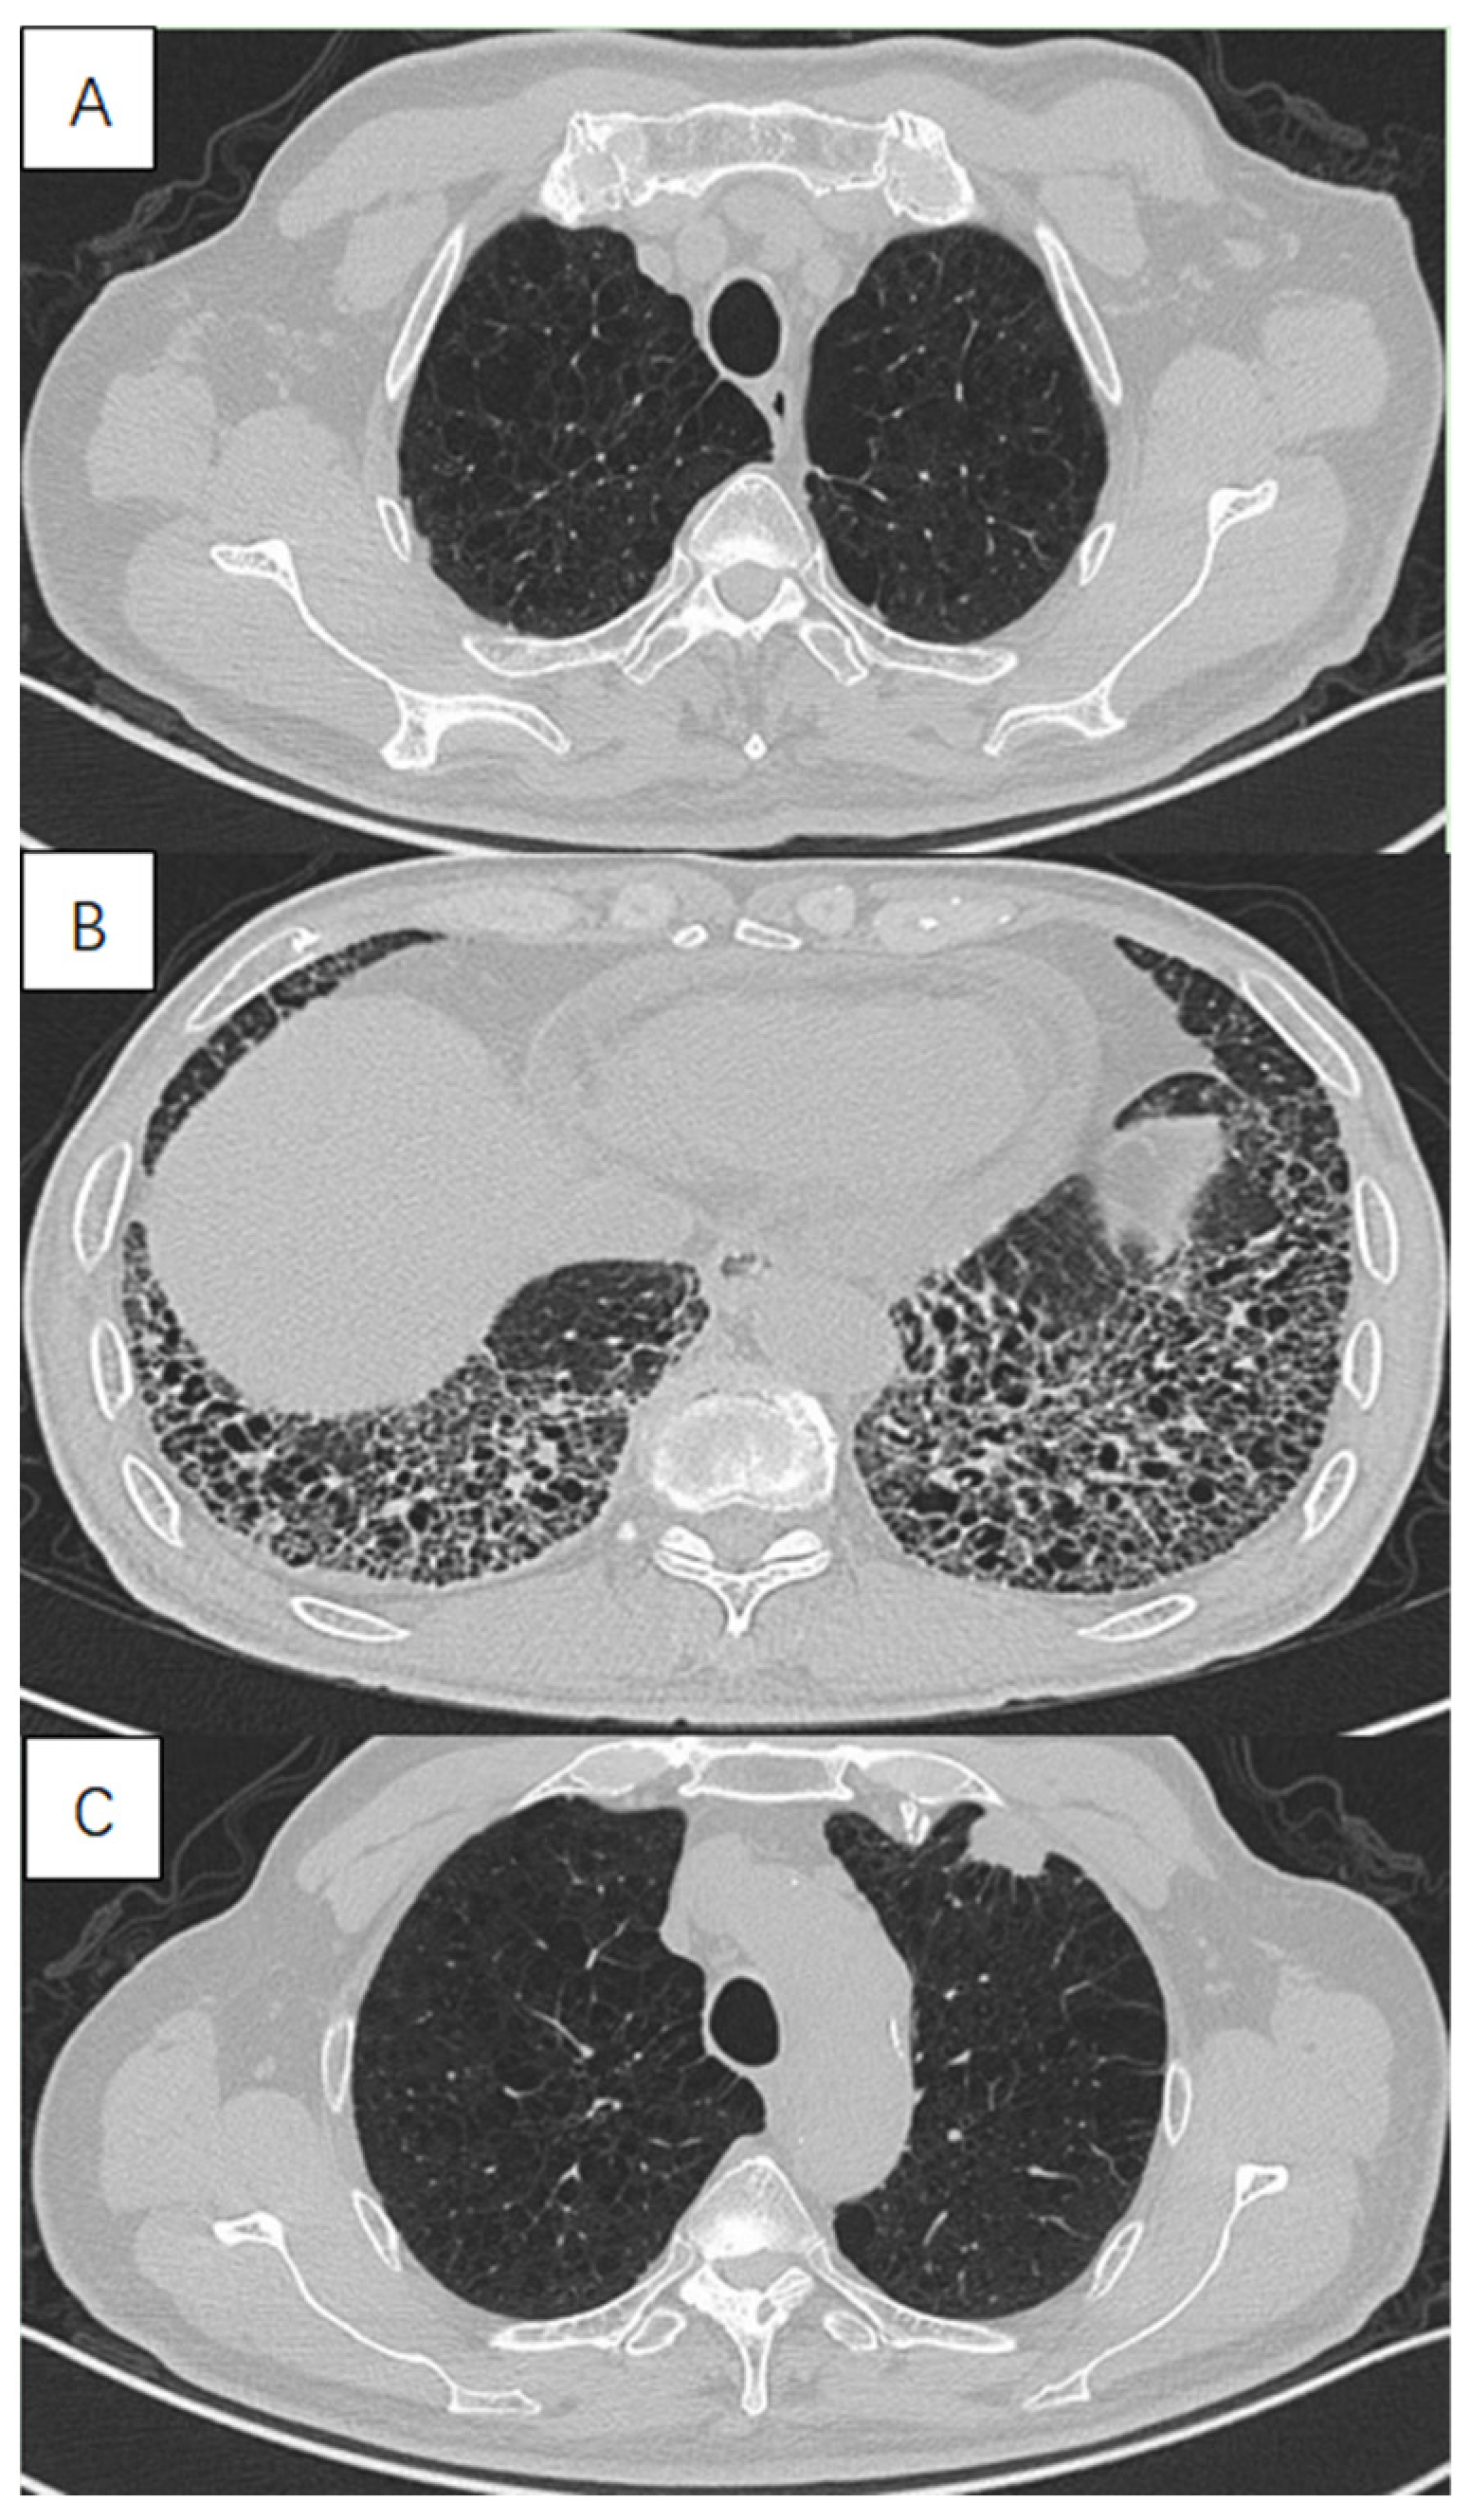

In this study we excluded patterns of lung fibrosis different from usual interstitial pneumonia (UIP) including typical grid shadow, honeycombing and traction bronchiectasis in subpleural and lower lung distribution. The UIP was diagnosed on the presence of a definite or probable UIP pattern based on the 2018 ATS/ERS/JRS/ALAT official IPF diagnosis and management guidelines [22]. All the diagnoses were ultimately made by two senior respiratory physicians and one radiologist on the basis of comprehensive consideration of clinical symptoms and imaging findings (Figure 1).

Figure 1.

High-resolution computed tomography in a 72-year-old male with lung cancer with combined pulmonary fibrosis and emphysema (CPFE), showing (A) paraseptal emphysema in the upper lobe, (B) lower-zone-predominant fibrosis and (C) a solid mass in the subpleural emphysema area in the left upper lobe.